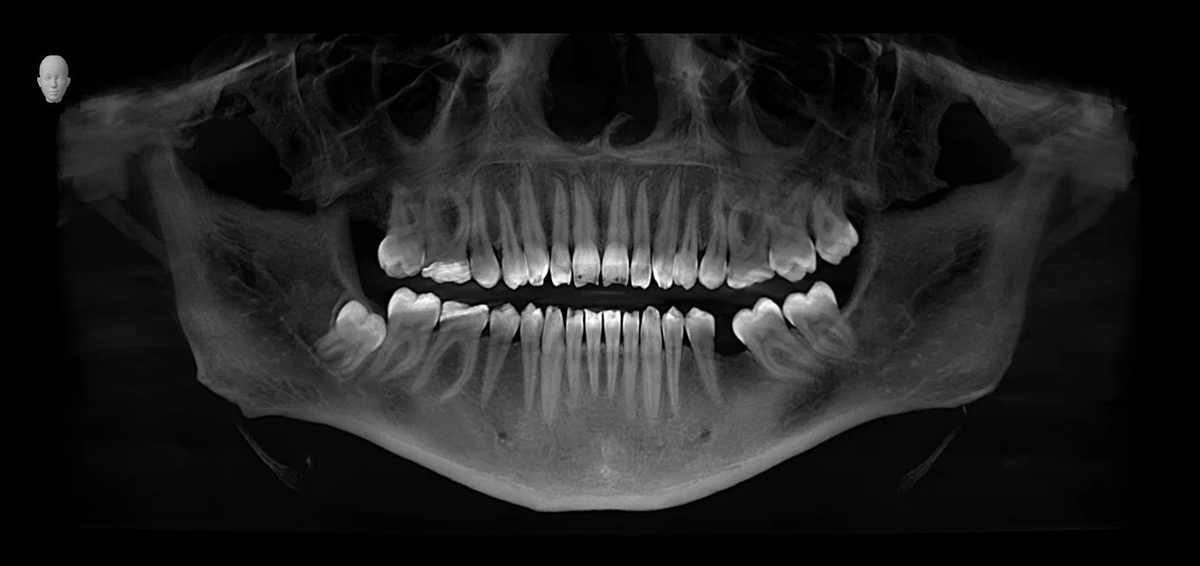

Имплант — это титановый штифт, который хирург устанавливает в кость. После операции начинается процесс заживления и адаптации тканей — он называется остеоинтеграцией.

Объем вмешательства

• Если установили один имплант — чаще всего вы сможете идти на работу уже на следующий день.

• После множественной имплантации или костной пластики может понадобиться 2–3 дня отдыха.

• Используем цифровое моделирование операции и навигационные шаблоны для точной установки имплантов.